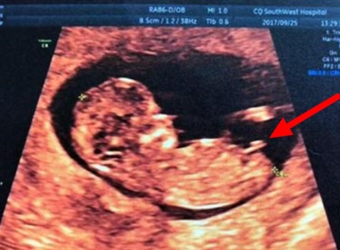

网上流传着四维彩超的报告上如果是有三条线就是女孩,而如果没有三条就是男孩,那么四维女宝宝三条线特征图片长什么样呢,四维男宝也有三条线吗?更多关于生男…

四维超声是一种比较先进的检查方式,也是实时的动态三维超声,一般来说通过四维超声来辨别宝宝性别是比较准确的,四维单子上出现了四个字的就是怀了男宝,更多…